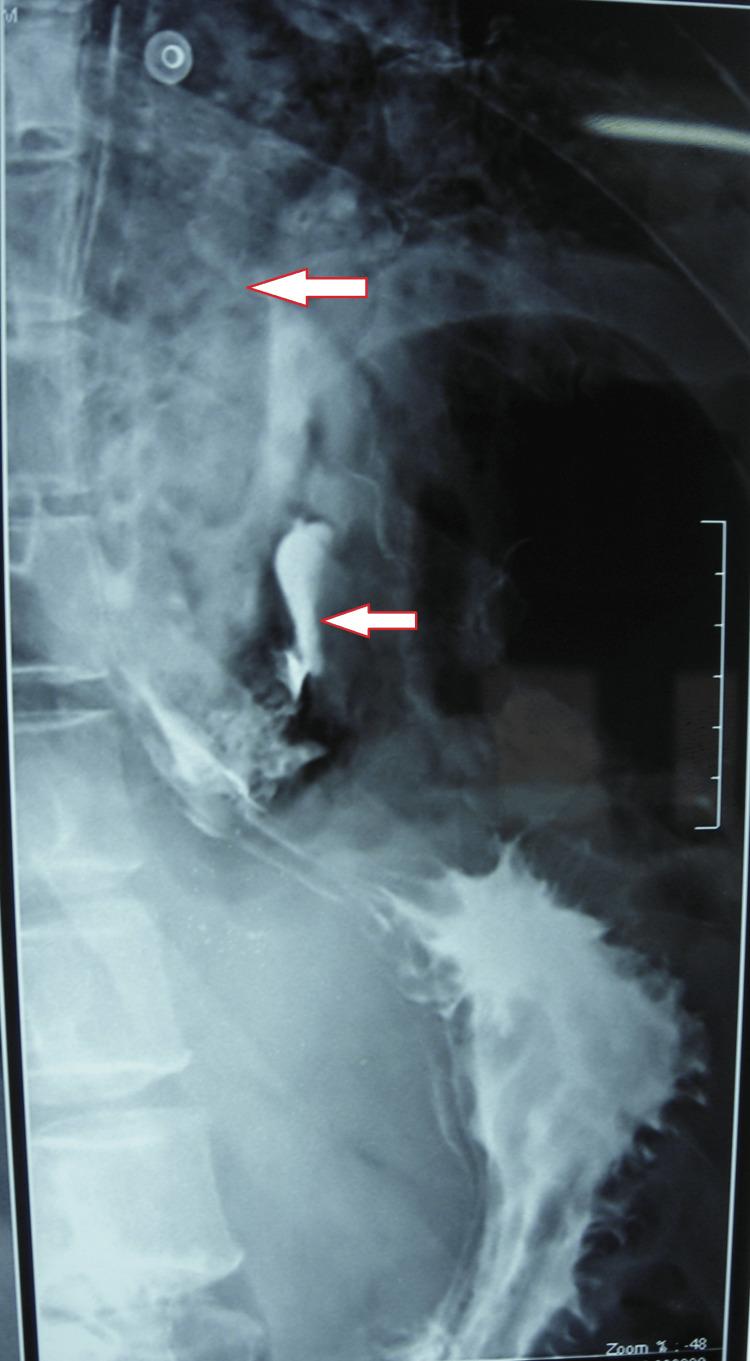

一例保守治疗的Boerhaave综合征病例报告

A Case Report of Conservatively Managed Boerhaave Syndrome.

Boerhaave syndrome is an esophagal perforation due to a rupture of the esophagus wall caused by intense vomiting with mediastinitis and subcutaneous emphysema. It is a relatively rare and potentially life-threatening ailment that requires prompt diagnosis and treatment. This case presents an overview of the syndrome, including morbidity, mortality, and treatment strategy. In this case, a 56-year-old male presented to the hospital during emergency hours with shortness of breath, chest pain, and dullness in the neck and a history of binge alcohol abuse seven days ago, followed by a severe bout of vomiting. The patient was managed conservatively, requiring another hospitalization for surgery, and was later discharged from the hospital postoperatively without any complications.

摘要